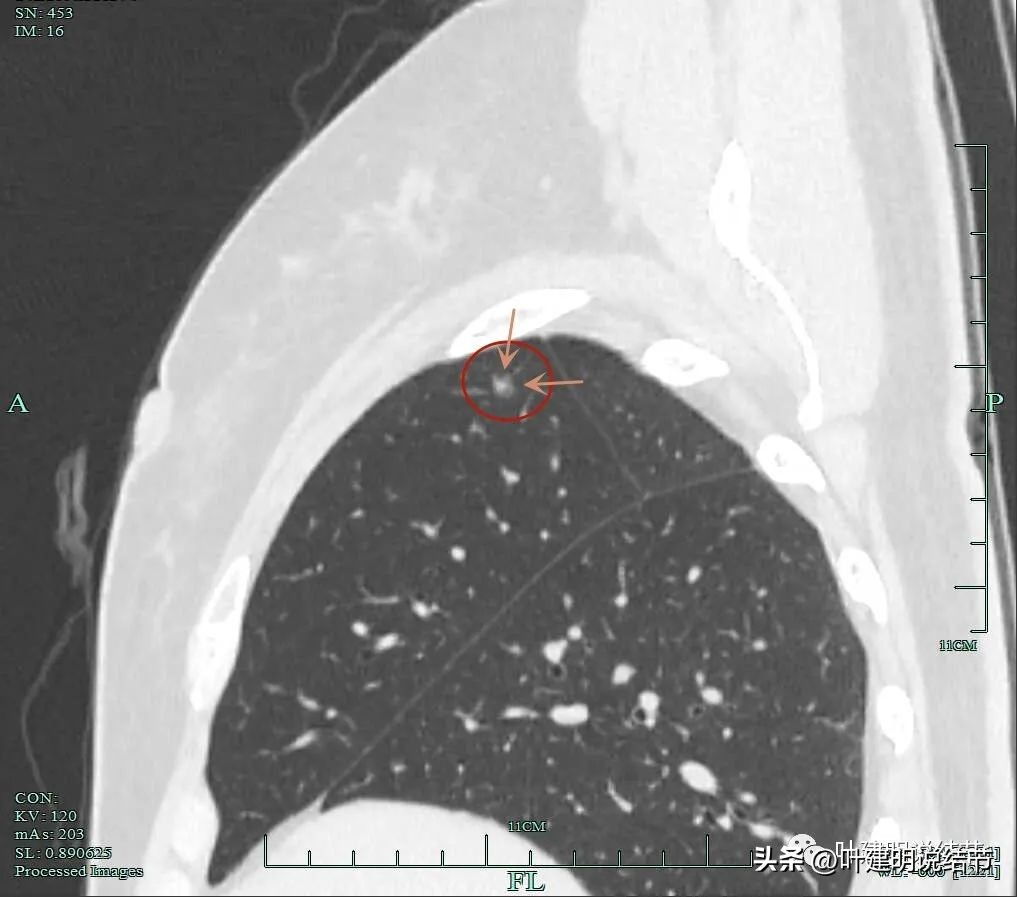

混合磨玻璃密度,轮廓与瘤肺边界清。

血管进入,局部细毛刺样征,轮廓清楚。

这个结节虽然不大,但整体轮廓清,瘤肺边界清楚,混合磨玻璃密度,有多支血管进入,进入灶内的血管增粗毛糙穿行,部分边缘还有细毛刺征,是较为典型的恶性影像表现。应该予以手术治疗为宜。